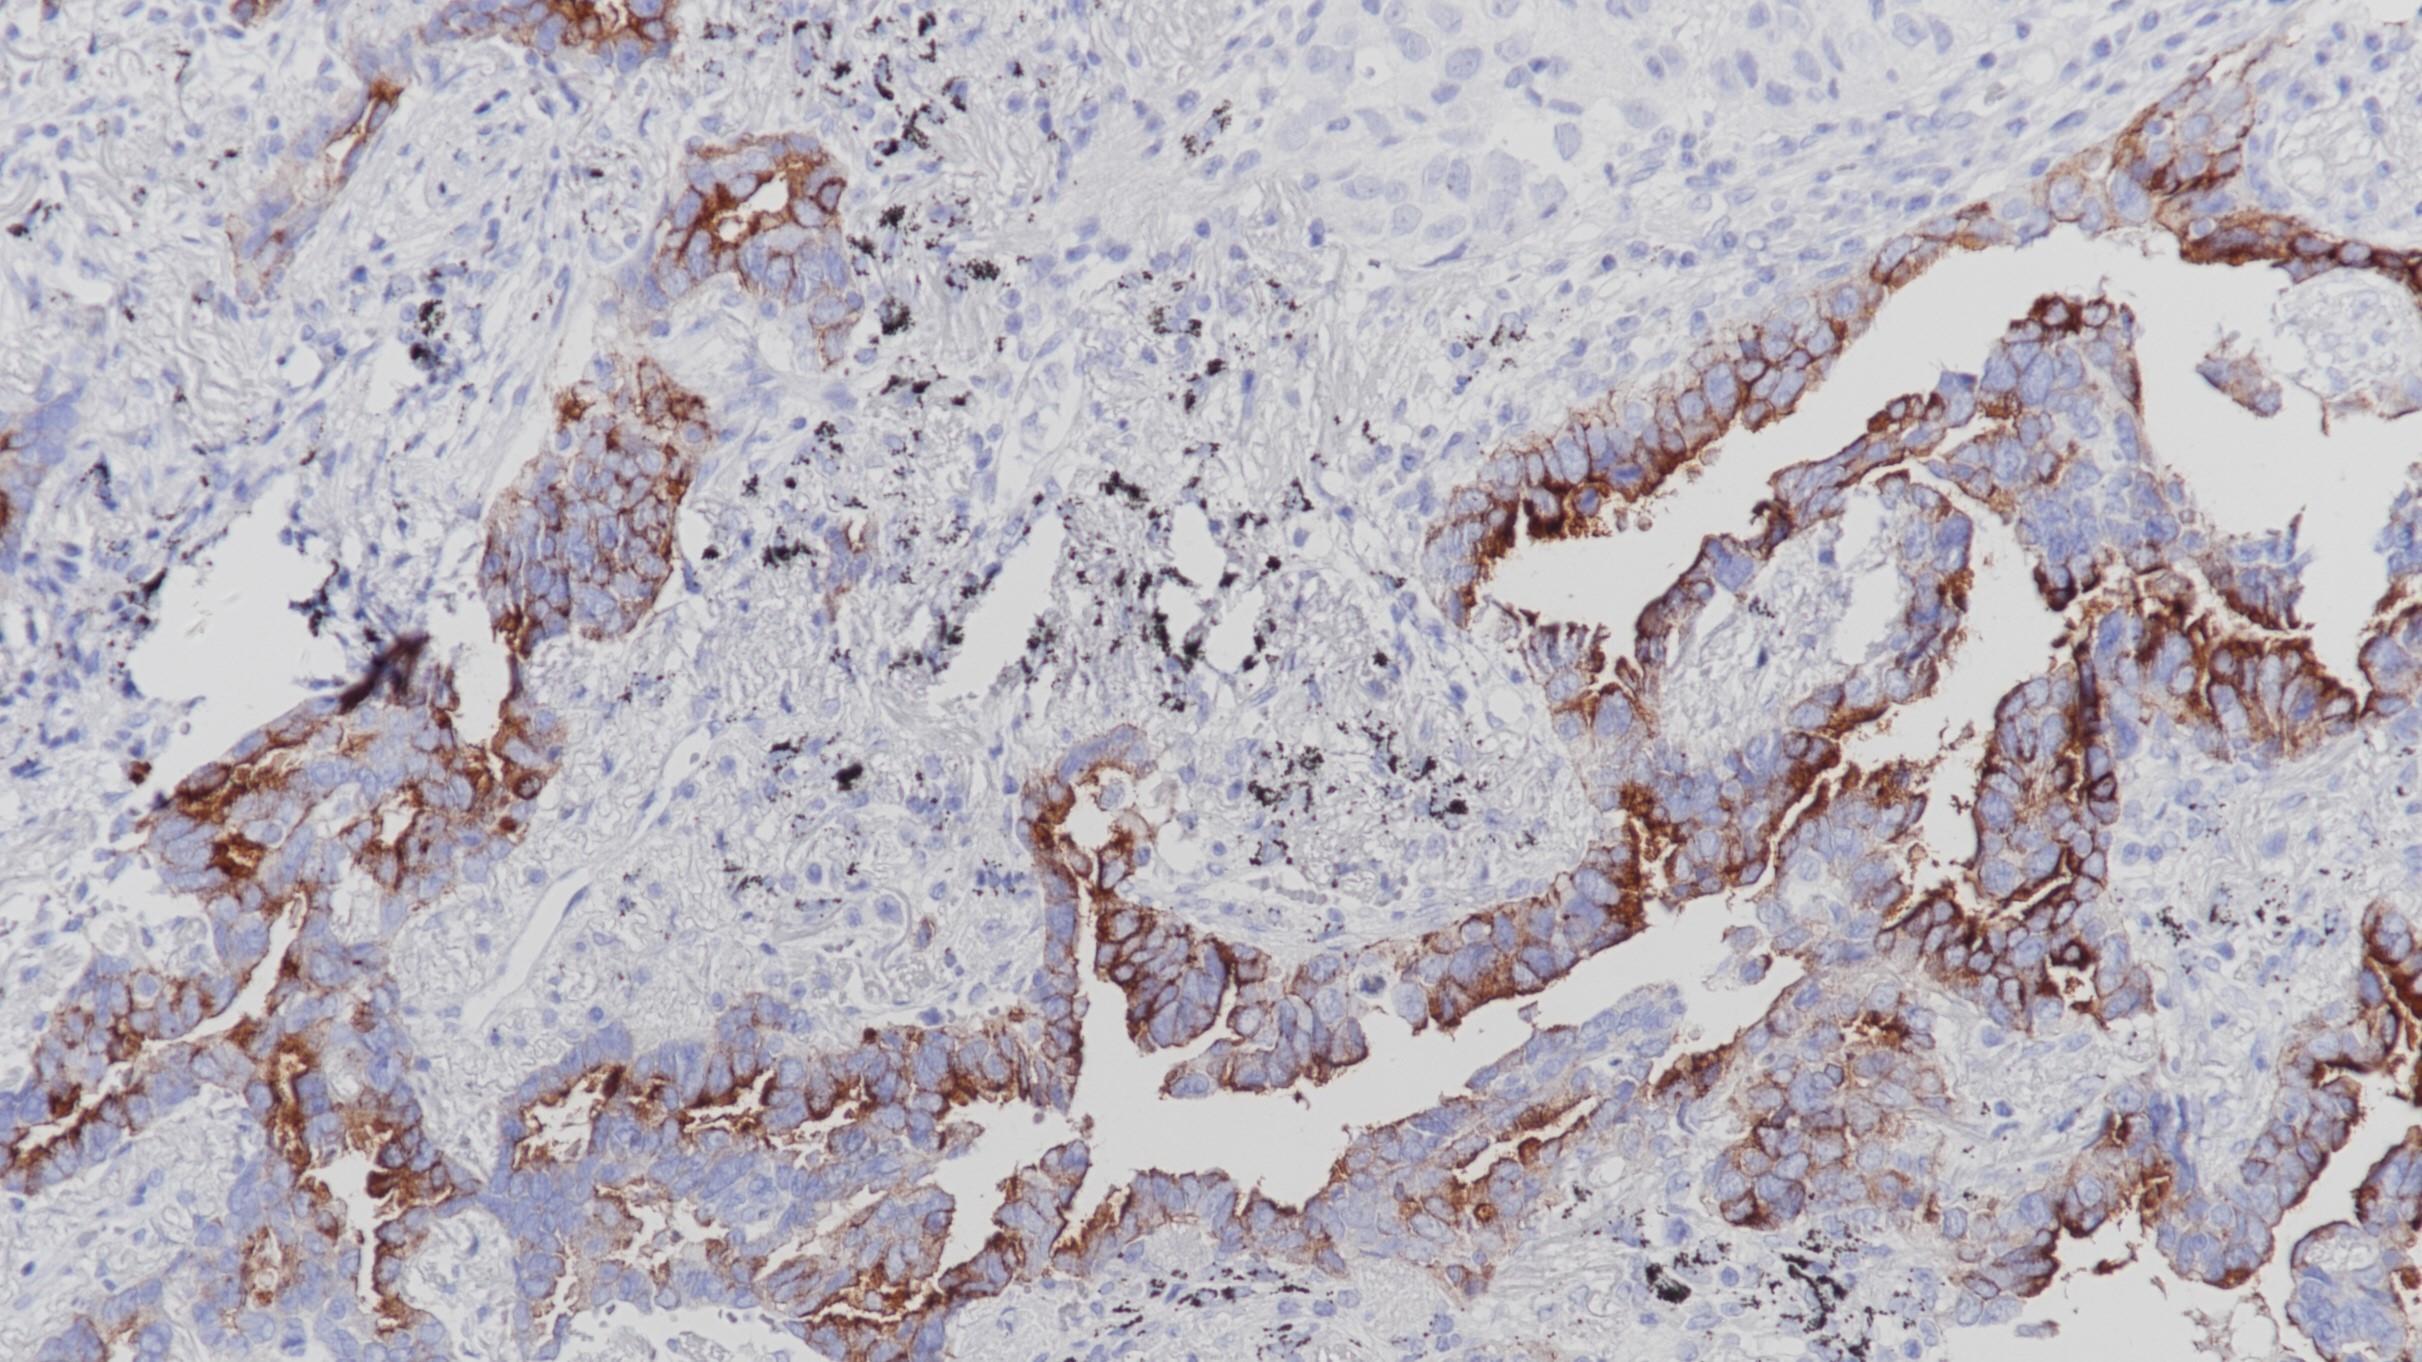

乳腺癌 FoxP3(BP6166)染色

Forkhead box (Fox)蛋白是一个高度进化的保守转录因子家族,包含一个被称为Forkhead box或翼状螺旋DNA结合域的序列。FoxP亚家族有四个成员,FoxP1 - FoxP4。FoxP蛋白通常作为转录抑制因子。FOXP3在成人、T细胞白血病或淋巴瘤扁桃体中活化的T淋巴细胞中表达,在器官发育、免疫应答和癌症发病中发挥重要作用。

亚细胞定位